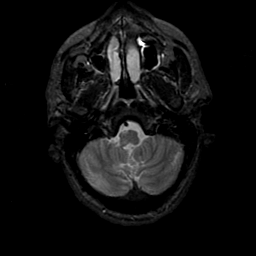

MR Study #21, November 3, 1991 -- Slice #7